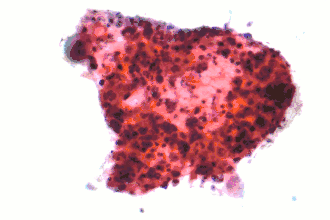

| Micrografia de um carcinoma escamoso, um tipo de carcinoma de pulmão não pequenas células. Espécime obtido por PAAF. Coloração de Papanicolau. | |